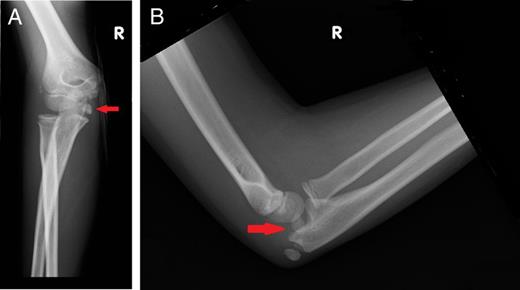

A 9-year-old girl presented to the emergency department with right elbow pain and swelling, after falling from a monkey bar onto her right elbow. She had no previous history of elbow or ulnar nerve problems. On examination, her right elbow was swollen, tender with limited movements. She had no history or clinical signs of an elbow dislocation, but she had a complete ulnar nerve palsy [with the absence of sensation and increased 2-point discrimination, Medical Research Council (MRC) sensation grading S0; MRC power grading 0/5 of intrinsic muscles of the hand, the little finger flexor digitorum profundus (FDP) and flexor carpi ulnaris (FCU); Froment's sign was positive), but there was no evidence of vascular compromise. A plain radiograph showed that the medial epicondylar apophysis had been avulsed into the ulna humeral joint space, but there was no other fracture or dislocation seen (Fig. 1A and B).

Plain radiographs of the injured right elbow: (A) anteroposterior view and (B) lateral view. Arrows highlight the avulsed medial epicondyle.